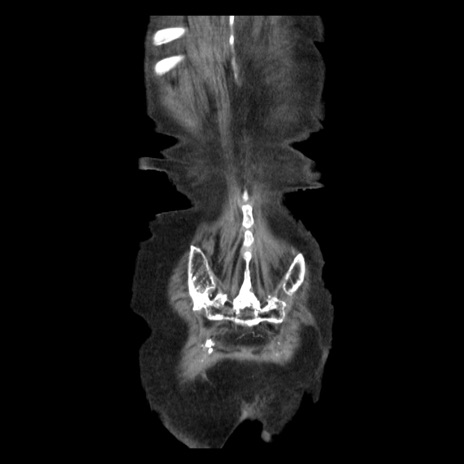

症例14(冠状断像)

【症例】 90歳代女性

【主訴】 腹痛・嘔吐

【現病歴】今朝から左側腹部痛を認めた。 経過観察していたが、嘔吐を認めたため来院。

【既往歴】 子宮癌術後

【身体所見】 意識清明、BP 127/54mmHg、P 98bpm Sp02 95%(RA)、BT 35.8°C、腹部平坦・軟腸ぜん動音聴取良好、右下腹部圧痛(+) 反跳痛なし

【データ】WBC 9800、CRP 0.46